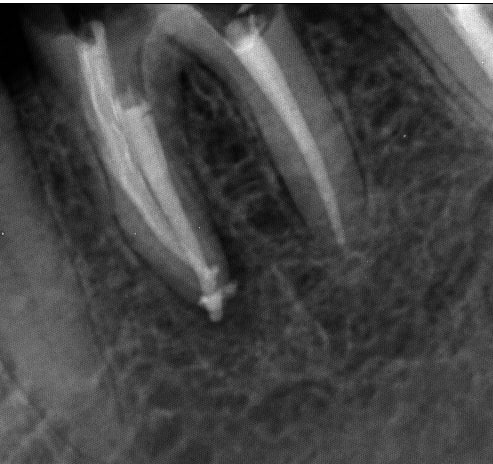

Juste pour prouver qu'on peut tout faire avec Mc Spadden, le derviche écossais:

Canal large, on est allé au F5 sans toucher les bords, cône calibré à 55 à l'apex, thermocompacteur à 3mm de la LT. Pas d'anesthésie.

21 ckpvf9 - Eugenol